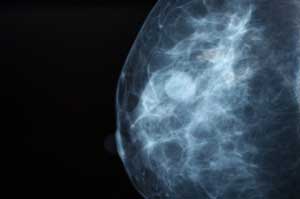

​El próximo viernes 17 de octubre, organizada por la Junta Local de Benahadux, tendrá lugar en el Salón de Plenos del Ayuntamiento una conferencia sobre Cáncer de Mama a cargo de la Dra. Mercedes Río.